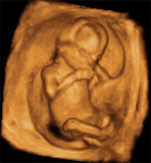

Desarrollo feto semana 28: Empieza a perder el lanugo

Ya estamos en la semana 28 de embarazo. La superficie de la piel está completamente cubierta de vérnix y acumula más grasa en su interior: esto que le dará el aspecto rollizo al nacer y de paso, le ayudará a soportar las frías temperaturas del mundo exterior. Recuerda que dentro de tu útero se encuentra a 36º C. A partir de ahora es posible que vaya perdiendo el lanugo, el vello que cubre ahora todo su cuerpo, aunque hay niños que nacen con restos en la espalda y en los hombros.

Cómo es el desarrollo del bebé en la semana 28

En la semana 28 de desarrollo fetal los párpados, hasta ahora fundidos, se separan. El hecho de practicar el abrir y cerrar los párpados le ayuda a perfeccionar el reflejo de parpadeo.

Mueve manos y pies

En ecografías de la semana 28 de gestación se pueden apreciar movimientos de flexión y extensión de los dedos de las manos que pueden interpretarse como la existencia del reflejo de asir. Cuando nazca, este será uno de los reflejos que observará el pediatra al nacer. Se llama reflejo de prensión palmar y plantar: al estimular la palma de la mano o del pie, el bebé flexiona inmediatamente los dedos. Incluso si agarra con dos sus manitas nuestros dedos lo hace con tal fuerza que será suficiente para levantar su propio peso.